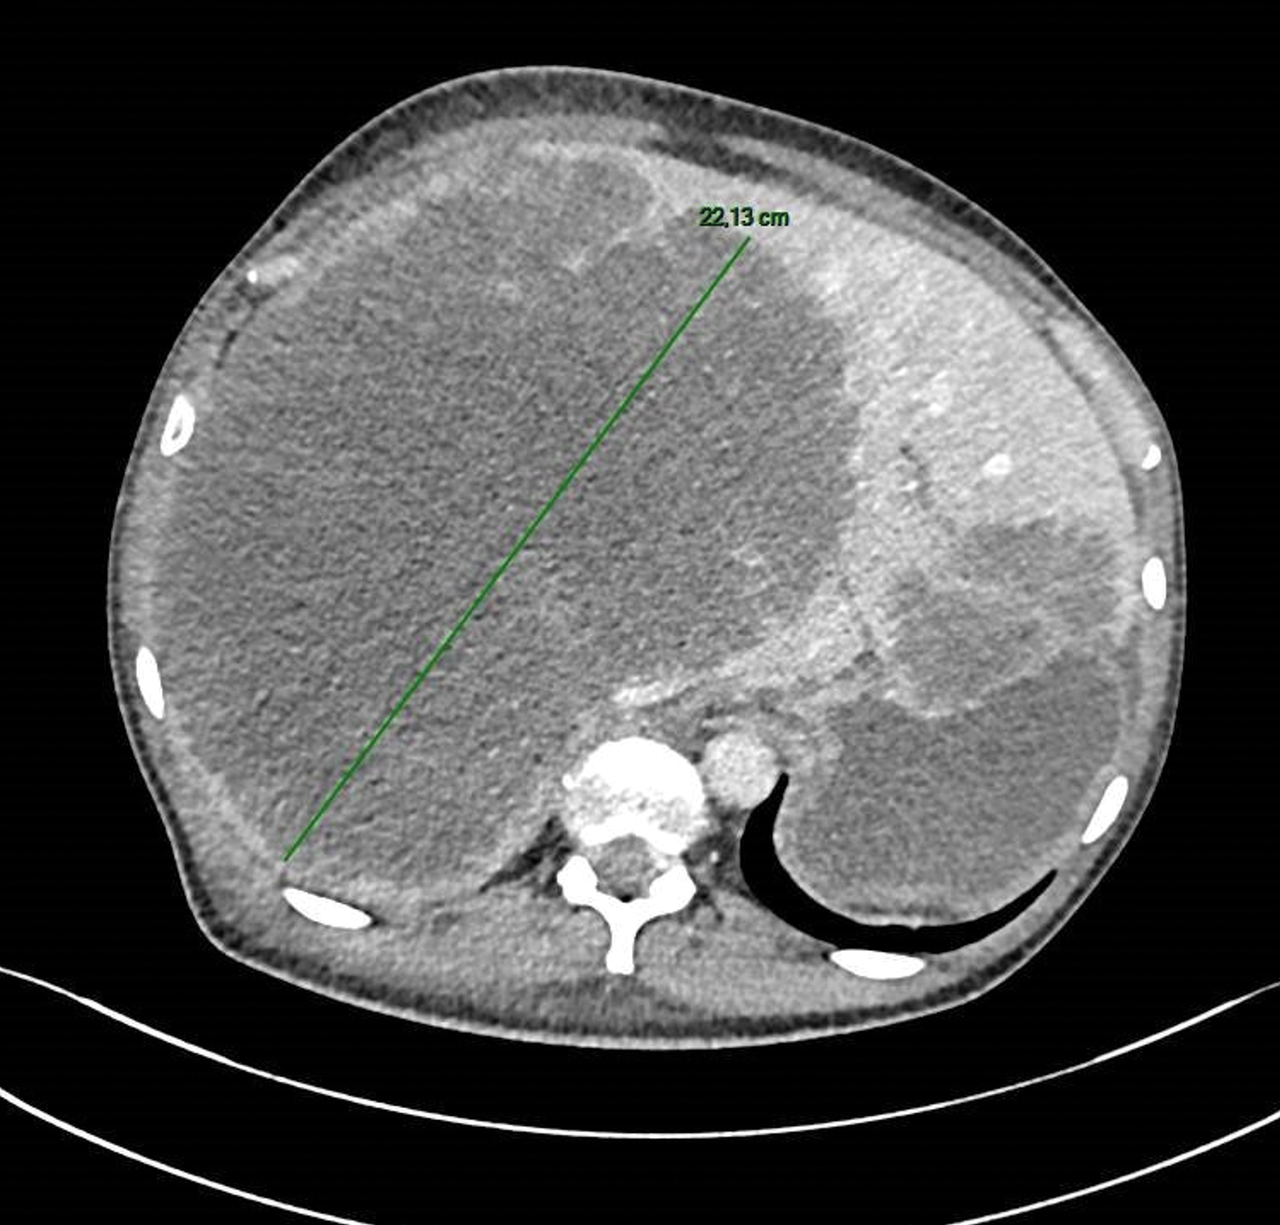

Un homme de 69 ans consulte pour des douleurs abdominales et une altération de l’état général.

Quel est votre diagnostic ?

La biopsie sous échographie met en évidence un adénocarcinome moyennement différencié d’origine colique.